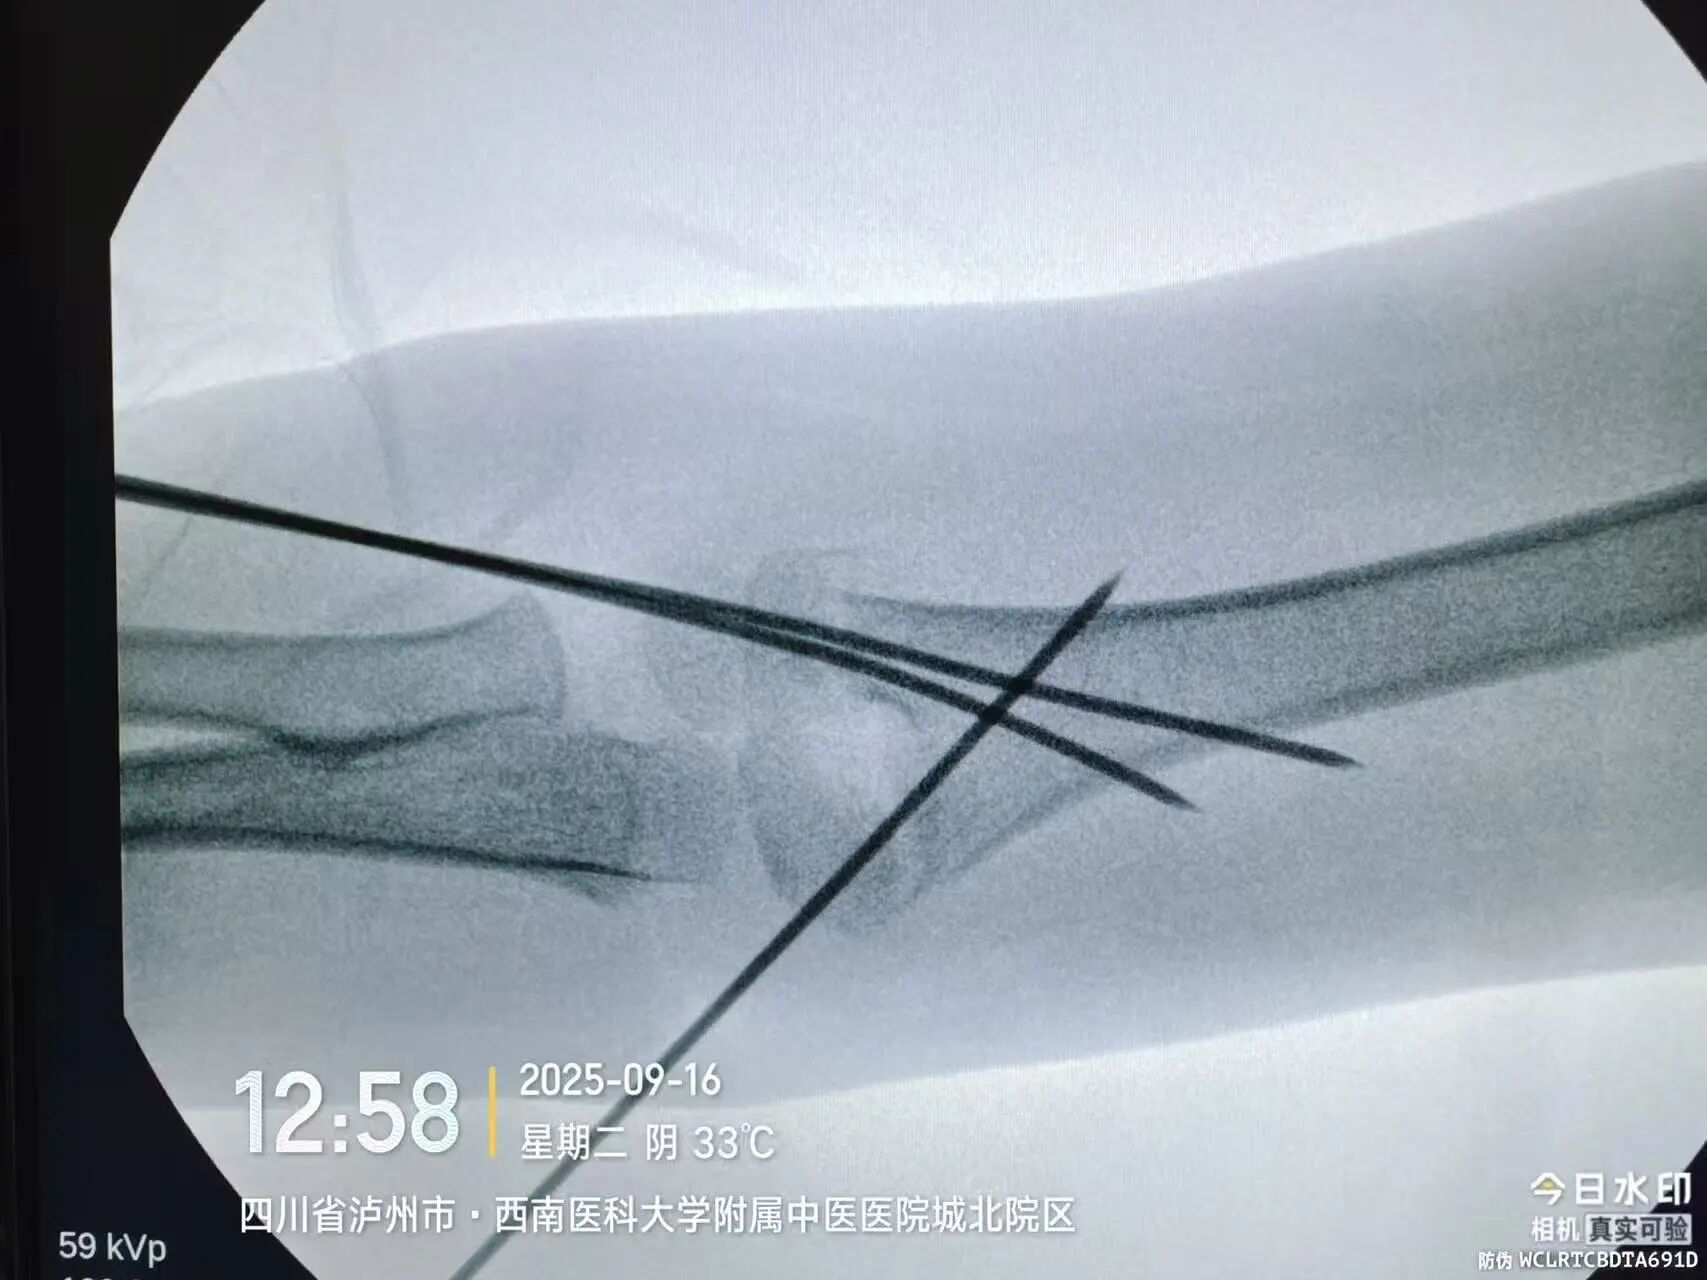

“孩子现在是最重要的初二,落下一周课就跟不上了!”小廖妈妈刚带孩子入院时,最焦虑的就是学习问题。让她意外的是,医院骨伤科手外·儿骨·烧伤整形组团队当即开通“儿童骨折急诊绿色通道”,仅用18小时就完成了术前检查、评估和桡骨远端骨折闭合复位经皮固定术。

同样“抢时间”的还有小罗和小周的治疗:4岁小罗9月15日深夜入院,10小时后顺利手术;7岁小周同一晚受伤,也在10小时内完成肱骨髁上骨折闭合复位经皮固定术。6岁小郑更是创下“4小时极速手术”纪录——早晨7点40分受伤,8点多入院,11点多手术结束,当天下午就能躺上网课。